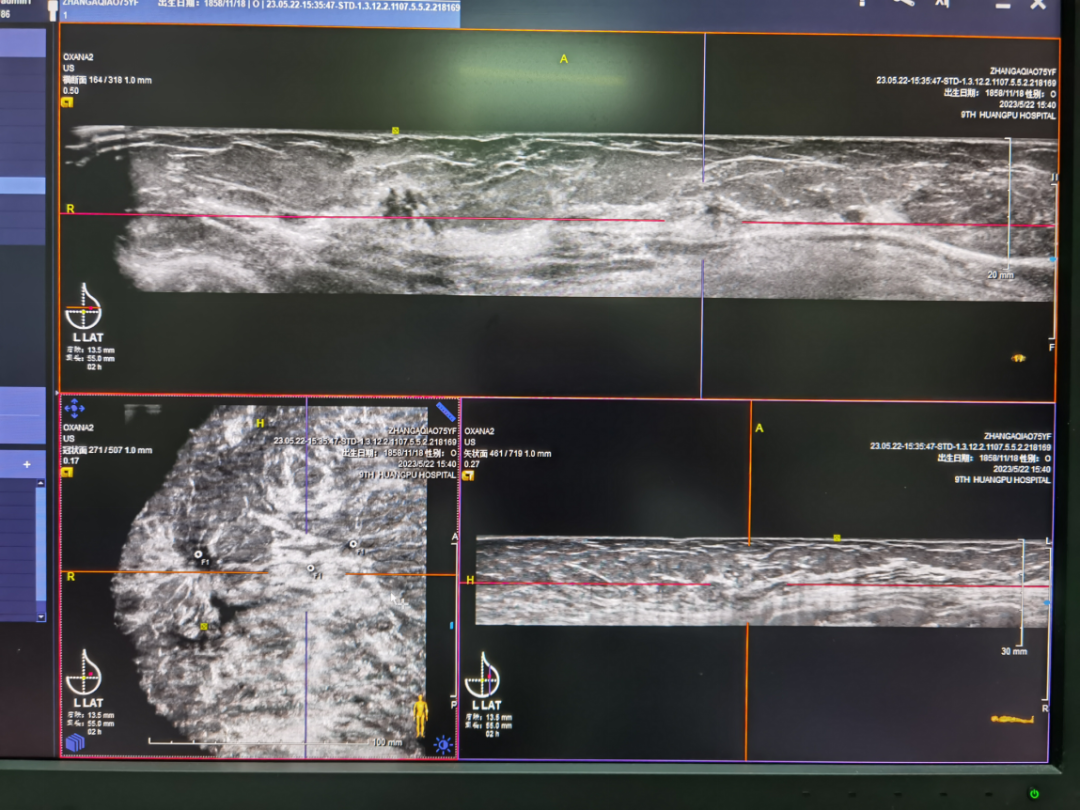

此病例为多病灶的浸润性乳腺癌患者,在手持式超声扫查时发现左乳头上方及外上方近乳腺边缘的两个病灶,术前磁共振检查发现三个病灶,再行ABVS检查,发现中间还有一个小子灶。入我院手术,病理证实小子灶为浸润性乳腺癌。

● ABVS检查